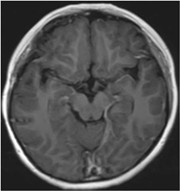

目前,患者22岁,体格仍较同龄人偏小,但身体上无其他不适症状,已正常参加工作。

2017年10月 放疗后6年余